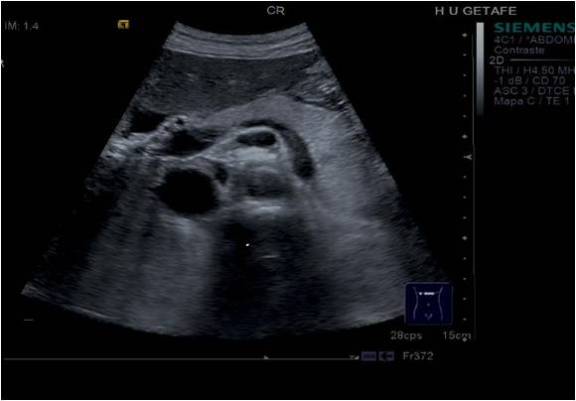

Ecográficamente, el Páncreas es una estructura que tiene normalmente una aspecto alargado, hiperecogénico y homogéneo, pero depende muchísimo de cada anatomía y de la edad del sujeto estudiado, pudiendo presentar infinidad de aspectos. Con la edad el órgano pierde grosor y se hace más delgado, perdiendo volumen.

Se observa en las imágenes anteriores las diferencias entre ambas estructuras según la edad, pero también influyen otros condicionantes, como la constitución más obesa o no de un paciente, por ejemplo.